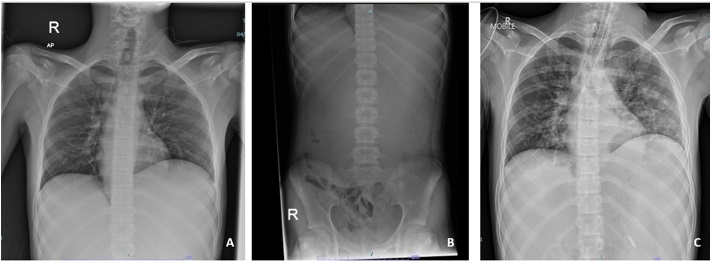

Superior mesenteric artery syndrome (SMAS), or Wilkie’s syndrome, is a rare cause of duodenal obstruction, whereby the duodenum is compressed between the superior mesenteric artery (SMA) and abdominal aorta (AA) due to a loss of mesenteric fat pad. This condition is associated with high morbidity and mortality, particularly if the diagnosis is delayed, leading to complications such as gastric perforation or aspiration pneumonia. A 14-year-old boy with an underlying severe autism spectrum disorder, complained of a two-day history of abdominal pain and vomiting, suggestive of gastric outlet obstruction, leading to hyperlactatemia and metabolic acidosis. An immediate contrast-enhanced computerised tomography revealed a significant dilatation of the lower esophagus until the D3 segment of the duodenum, narrowing of the aortomesenteric angle, and shortening of the aortomesenteric distance, findings suggestively of duodenal obstruction secondary to SMAS. However, patient subsequently developed persistent vomiting leading to aspiration pneumonia. He rapidly deteriorated into septic shock with multiorgan failure, ultimately leading to his death. This case report aimed to highlight the challenges in diagnosing and managing SMAS particularly in autistic children as they may have difficulty communicating their distress, and there is a potential of rapid deterioration that requires prompt escalation of care.